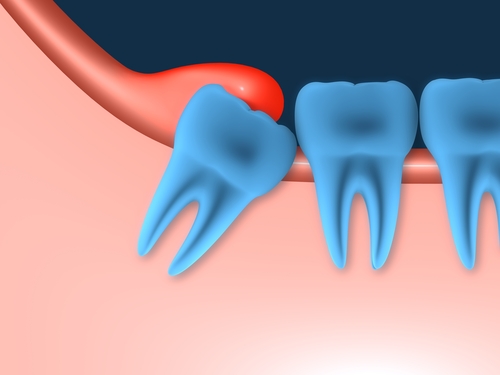

שן כלואה

שיניים כלואות הן שיניים המאחרות לבקוע זמן רב מעל הגיל הממוצע לבקיעתן. הסיכויים לבקיעתם הטבעית של שיניים כלואות הם נמוכים באופן כללי.